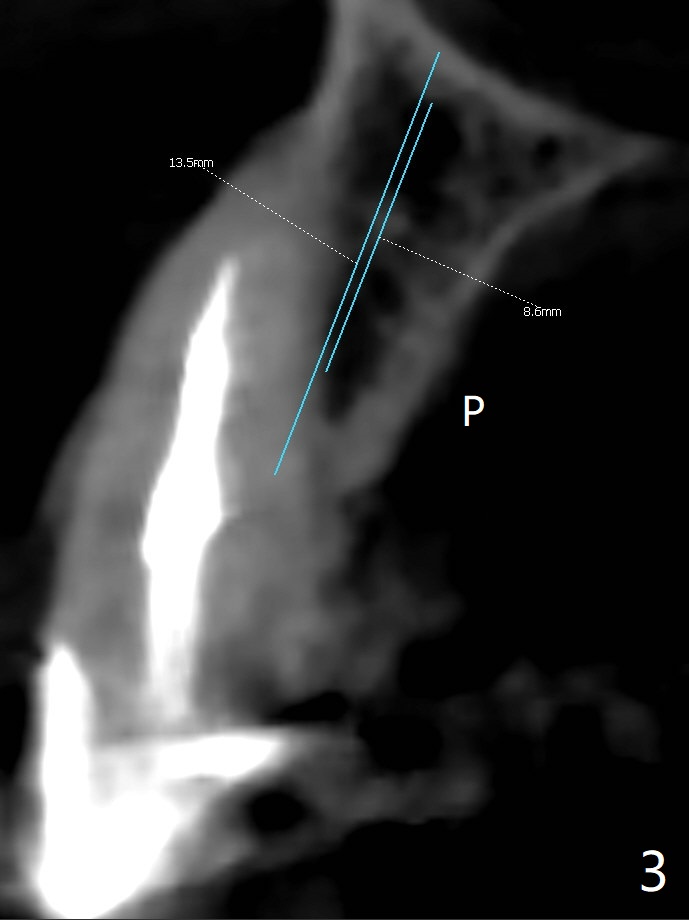

60岁女比较瘦小,8个月前因右下4,5轻度植体周围炎(4.5毫米软组织水平两段式植体种得太颊侧)就诊,准备重做,后来由于口腔卫生改善,症状减轻,她不愿意手术。右下6种植两个2.5x10毫米一段式种植。最近右上尖牙折裂,部分龈下(图一),她果断选择拔除种植。根尖片显示足够空间植入4.5x20毫米软组织水平植体(图二)。8个月前拍摄CT冠状面表明有充分根尖骨质(图三),植入3x14毫米骨水平一段式植体,便有2毫米颊侧,腭侧骨壁(减少植体周围炎可能性),而且修复角度优越(图四)。我可能在腭侧牙槽窝下1/3骨壁垂直钻入,然后改变钻洞方向,如红线,临床上,由咬合关系决定方位。如果不行,我有15度一段式植体。Bendable植体来不及买了。